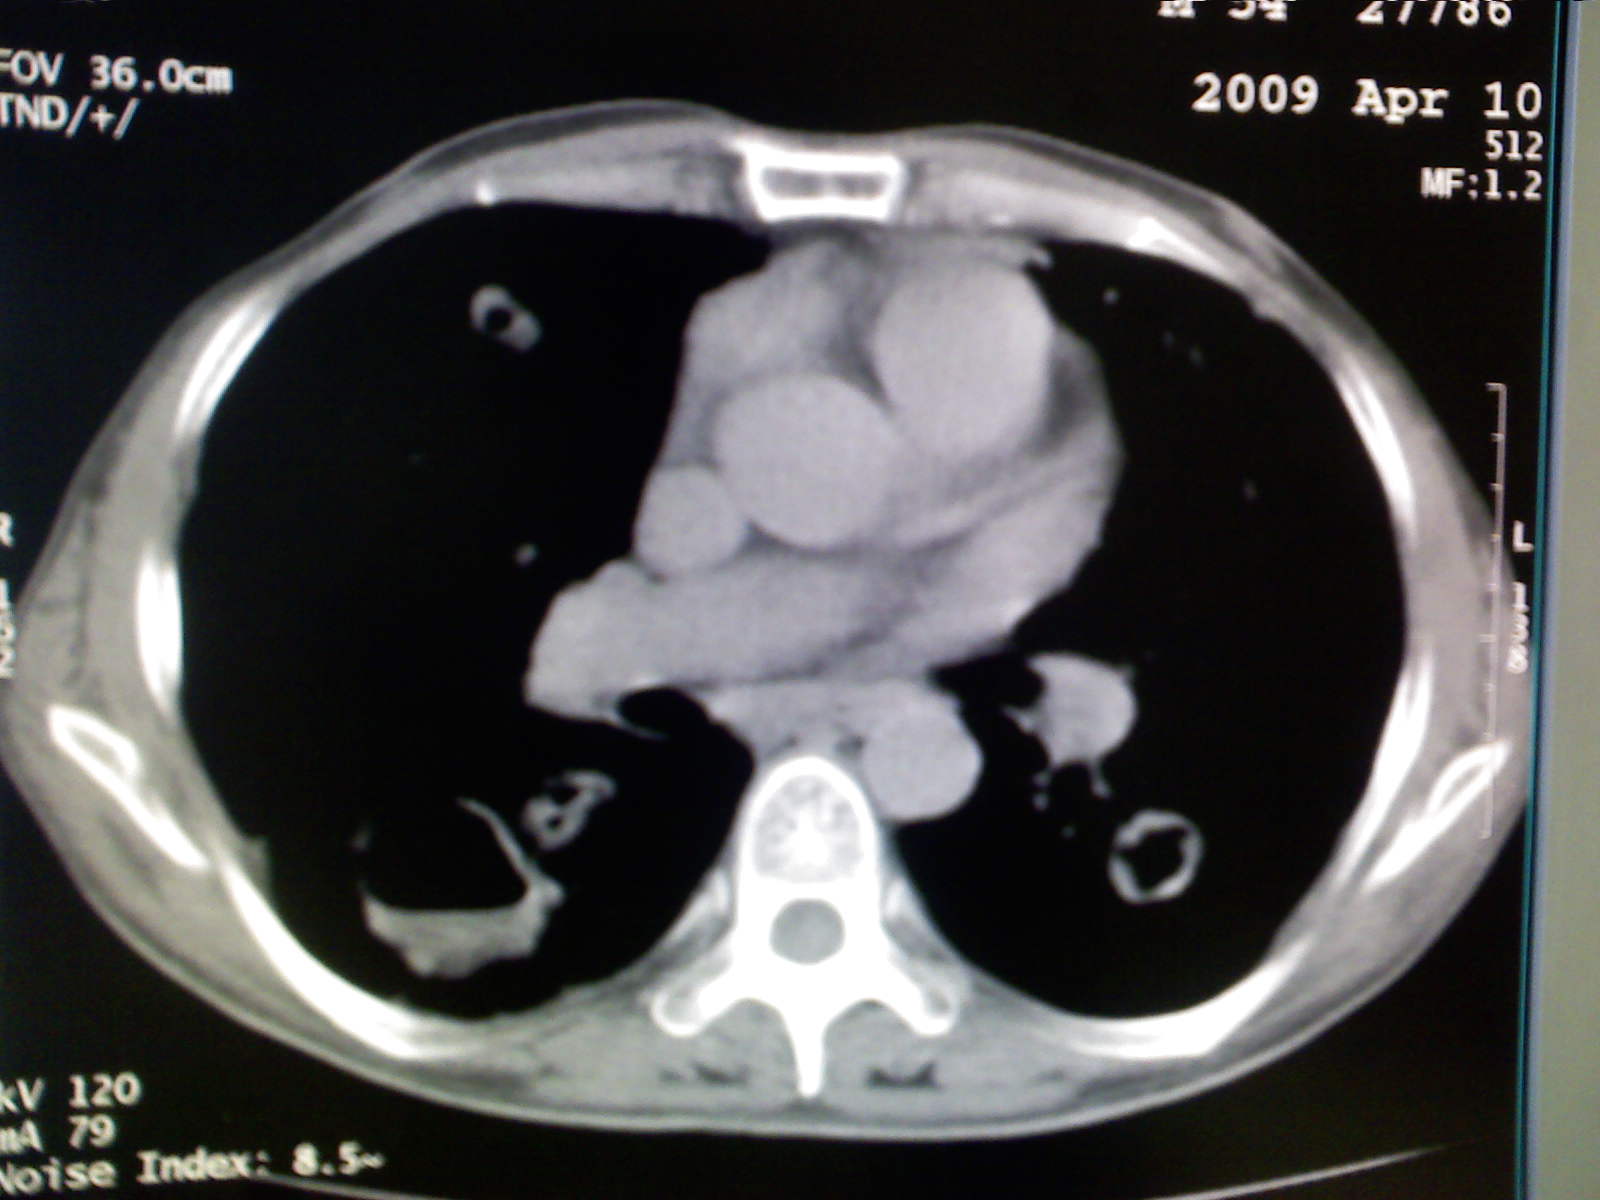

以下是引用卜一在2009-4-11 15:50:00的发言:[br]双肺继发性肺结核伴空洞形成,不排除合并霉菌感染!(病灶呈多形态 多特征 散在分布)。另:合并支气管扩张征伴感染!

以下是引用主力军在2009-4-11 15:55:00的发言:[br]两肺继发性肺结核可能性大。

以下是引用康鹏在2009-4-11 16:30:00的发言:[br]双肺继发性肺结核伴空洞形成合并感染[br]支气管扩张合并感染